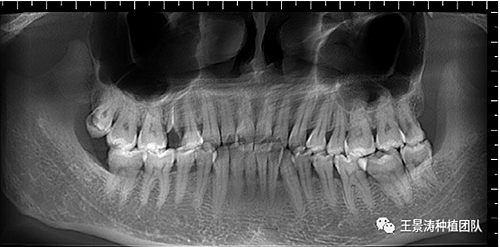

左側(cè)下頜第二磨牙及右側(cè)下頜第一磨牙同時(shí)即刻種植病例?;颊吣贻p女性,無系統(tǒng)性疾病。37及46殘冠及殘根,且46劈裂,無法冠修復(fù),必須拔除。37根尖慢性炎癥,大量肉芽組織存在,46根分叉較高,根分叉骨質(zhì)尚可。CBCT示:根尖骨質(zhì)至下牙槽神經(jīng)管距離可滿足種植體的初期穩(wěn)定性,遂考慮即刻種植,并在種植體周邊填入骨粉并覆蓋骨膜,雙側(cè)的種植體初期穩(wěn)定性相差無幾,但考慮到37根尖慢性炎癥較大,遂給予埋入式種植。